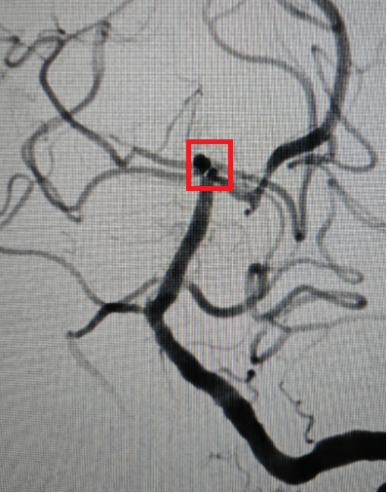

术后动脉瘤消失。

由于王先生颅内动脉瘤破裂伴蛛网膜下腔出血,根据其动脉瘤形状、大小与周边血管位置关系等特点,医师团队决定使用新型自膨式动脉瘤瘤内栓塞系统(WEB)为其扫除颅内“炸弹”。针对此类基底动脉顶端部位复杂动脉瘤,相较于传统开颅及介入手术,应用WEB装置系统稳定性更高,能够明显降低手术并发症率,缩短手术时间,免除抗血小板药物治疗等优点。这种方式属于微创治疗手段,借助血管内介入的方式将特殊的栓塞材料送进动脉瘤内,阻断血液流入动脉瘤,从而以更小的创伤封堵动脉瘤,为患者的恢复创造更好的条件。据悉,团队这次使用了VIA17的输送系统,20分钟内成功将瘤内扰流装置植入动脉瘤瘤腔内,完美封堵瘤颈,即时造影可见动脉瘤不再显影。手术结束后王先生转入ICU继续进一步治疗。